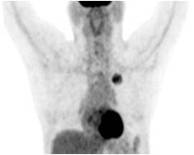

Cách thức điều trị: bệnh nhân được quyết định điều trị hóa chất phác đồ DC với liều Docetaxel (Taxotere) 75mg/m 2, truyền tĩnh mạch ngày 1, Carboplatin 300mg/m2, truyền tĩnh mạch ngày 1. Chu kỳ 3 tuần. Đánh giá sau 3 tuần. Bệnh nhân được điều trị hóa chất DC 3 chu kỳ. Đánh giá sau 3 tuần: Chụp PET/CT có đáp ứng tốt trên PET/CT.

Đáp ứng trên hình ảnh PET/CT như sau:

Khối u phổi trước điều trị: SUV=6,89 | Khối u phổi sau điều trị hóa chất 3 đợt: SUV=3,24 | Sau xạ trị và HC 6 đợt: khối u tan biến |